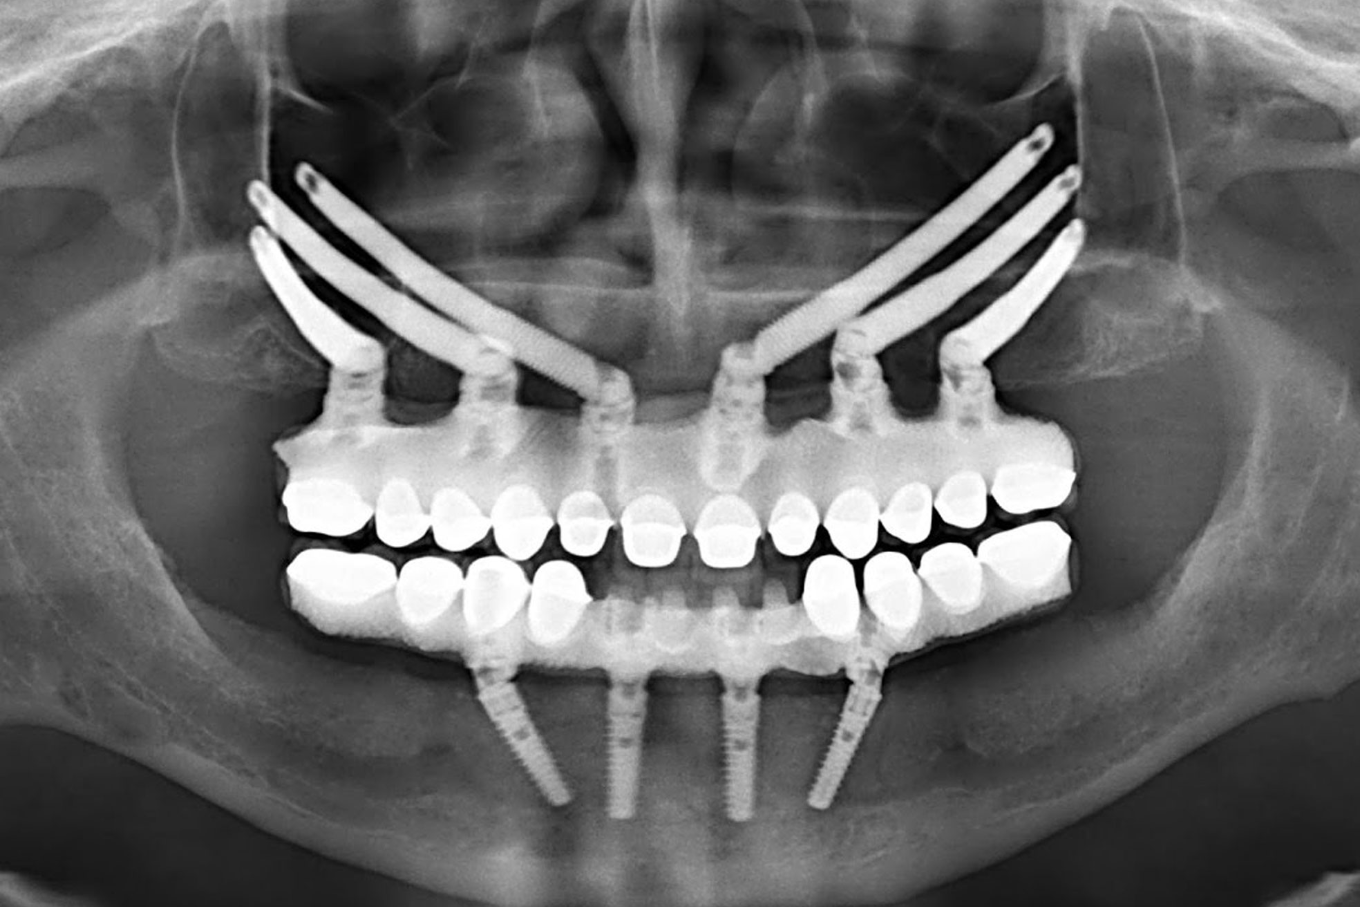

4. All on 4 hoặc All on 6

Dành cho người mất răng toàn hàm hoặc gần toàn hàm. Bác sĩ cấy 4 hoặc 6 trụ Implant vào vị trí chiến lược trên xương hàm, sau đó gắn hàm sứ cố định lên trên. Ăn nhai phục hồi lên đến 90% so với răng thật.

Tại San Dentist, All on 4 giá từ 131,2 triệu đồng/hàm (trụ Biotem). All on 6 từ 153,8 triệu đồng/hàm.

Với trường hợp tiêu xương nặng, bác sĩ có thể cân nhắc Implant Chân Bướm (27 triệu đồng) hoặc Implant Zygoma (38 triệu đồng), cấy vào xương gò má thay vì xương hàm, không cần ghép xương.